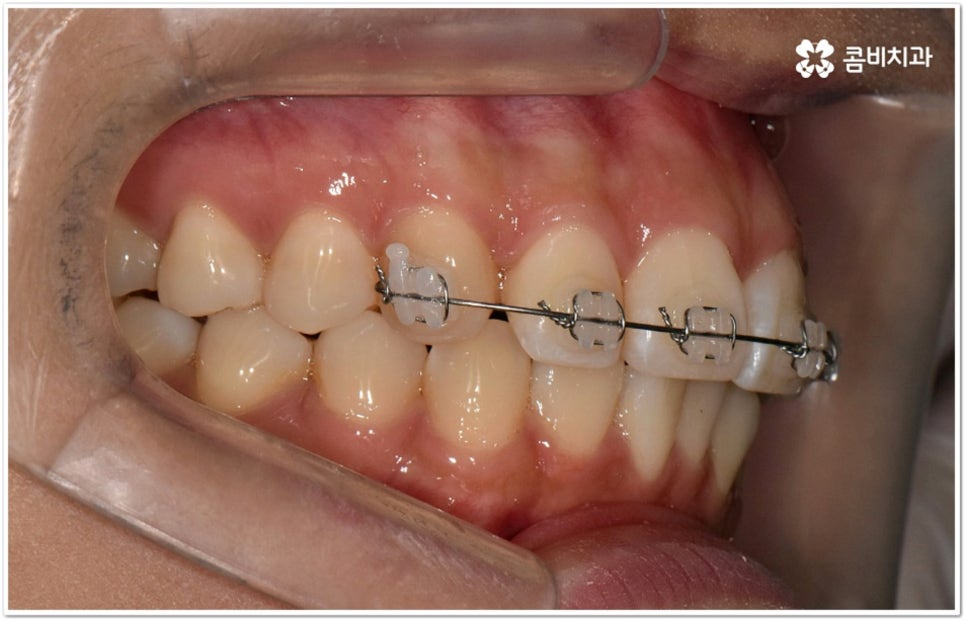

덧니의 원인에는 여러 가지가 있는데 대표적으로는 유치가 너무 일찍 빠져서 영구치가 제대로 자리를 잡지 못했거나 턱뼈의 크기와 치아 크기가 조화를 이루지 못하는 경우 등 공간이 부족한 상황을 생각해 볼 수 있어요. 덧니는 주로 송곳니가 가장 흔하나, 치열이 공간이 부족할 경우 이론적으로는 어떤 치아라도 덧니가 될 수 있어요. 이때 원인과 정도를 꼼꼼하게 파악하여 만약 해당 부위만 부분 교정이 가능하다면 덧니부분교정 치료를 할 수 있는데요. 덧니부분교정 을 이용하면 원하는 부위에만 브라켓을 부착하여 치아 이동을 시키기 때문에 전체 교정에 비해서 간편하며 치료 기간도 6~8개월 정도로 줄어들고 통증도 많이 감소될 수 있습니다. 비용적인 부담도 덜하며 (삐뚤어진 정도나 상태에 따라 다르겠지만) 보통 덧니부분교정 의 경우 비발치 과정으로 진행되기 때문에 환자분들의 입장에서는 덧니부분교정 을 많이 선호하시는 편이라고 할 수 있어요. 상황에 따라 미니스크류, 치간삭제, 악궁확장장치 등 환자에게 맞는 비발치 방법을 이용하여 도움 받을 수 있습니다.

요즘 가장 많이 쓰이는 클리피씨 장치는 이런 면에서 많은 장점을 가지고 있어요. 예전과 다른 자가 결찰 방식을 이용하기 때문에 마찰로 손실되는 교정력이 줄어들어 좀 더 적은 힘으로도 부드럽고 지속적인 치아 이동을 가능하게 하므로, 상황에 따라 다르지만 보통 6개월 정도의 기간 단축 및 이동시 초기에 느낄 수 있는 통증을 덜어준다고 할 수 있는데요. 그밖에도 치아 색상의 브라켓을 이용하여 심미성 또한 뛰어나며 상황에 따라 환자분들에게 맞게 내원 횟수도 줄여줄 수 있다고 하니 숙련된 의료진과 충분하게 상담해 보시고 신중한 선택하시길 권유드리고 있습니다.